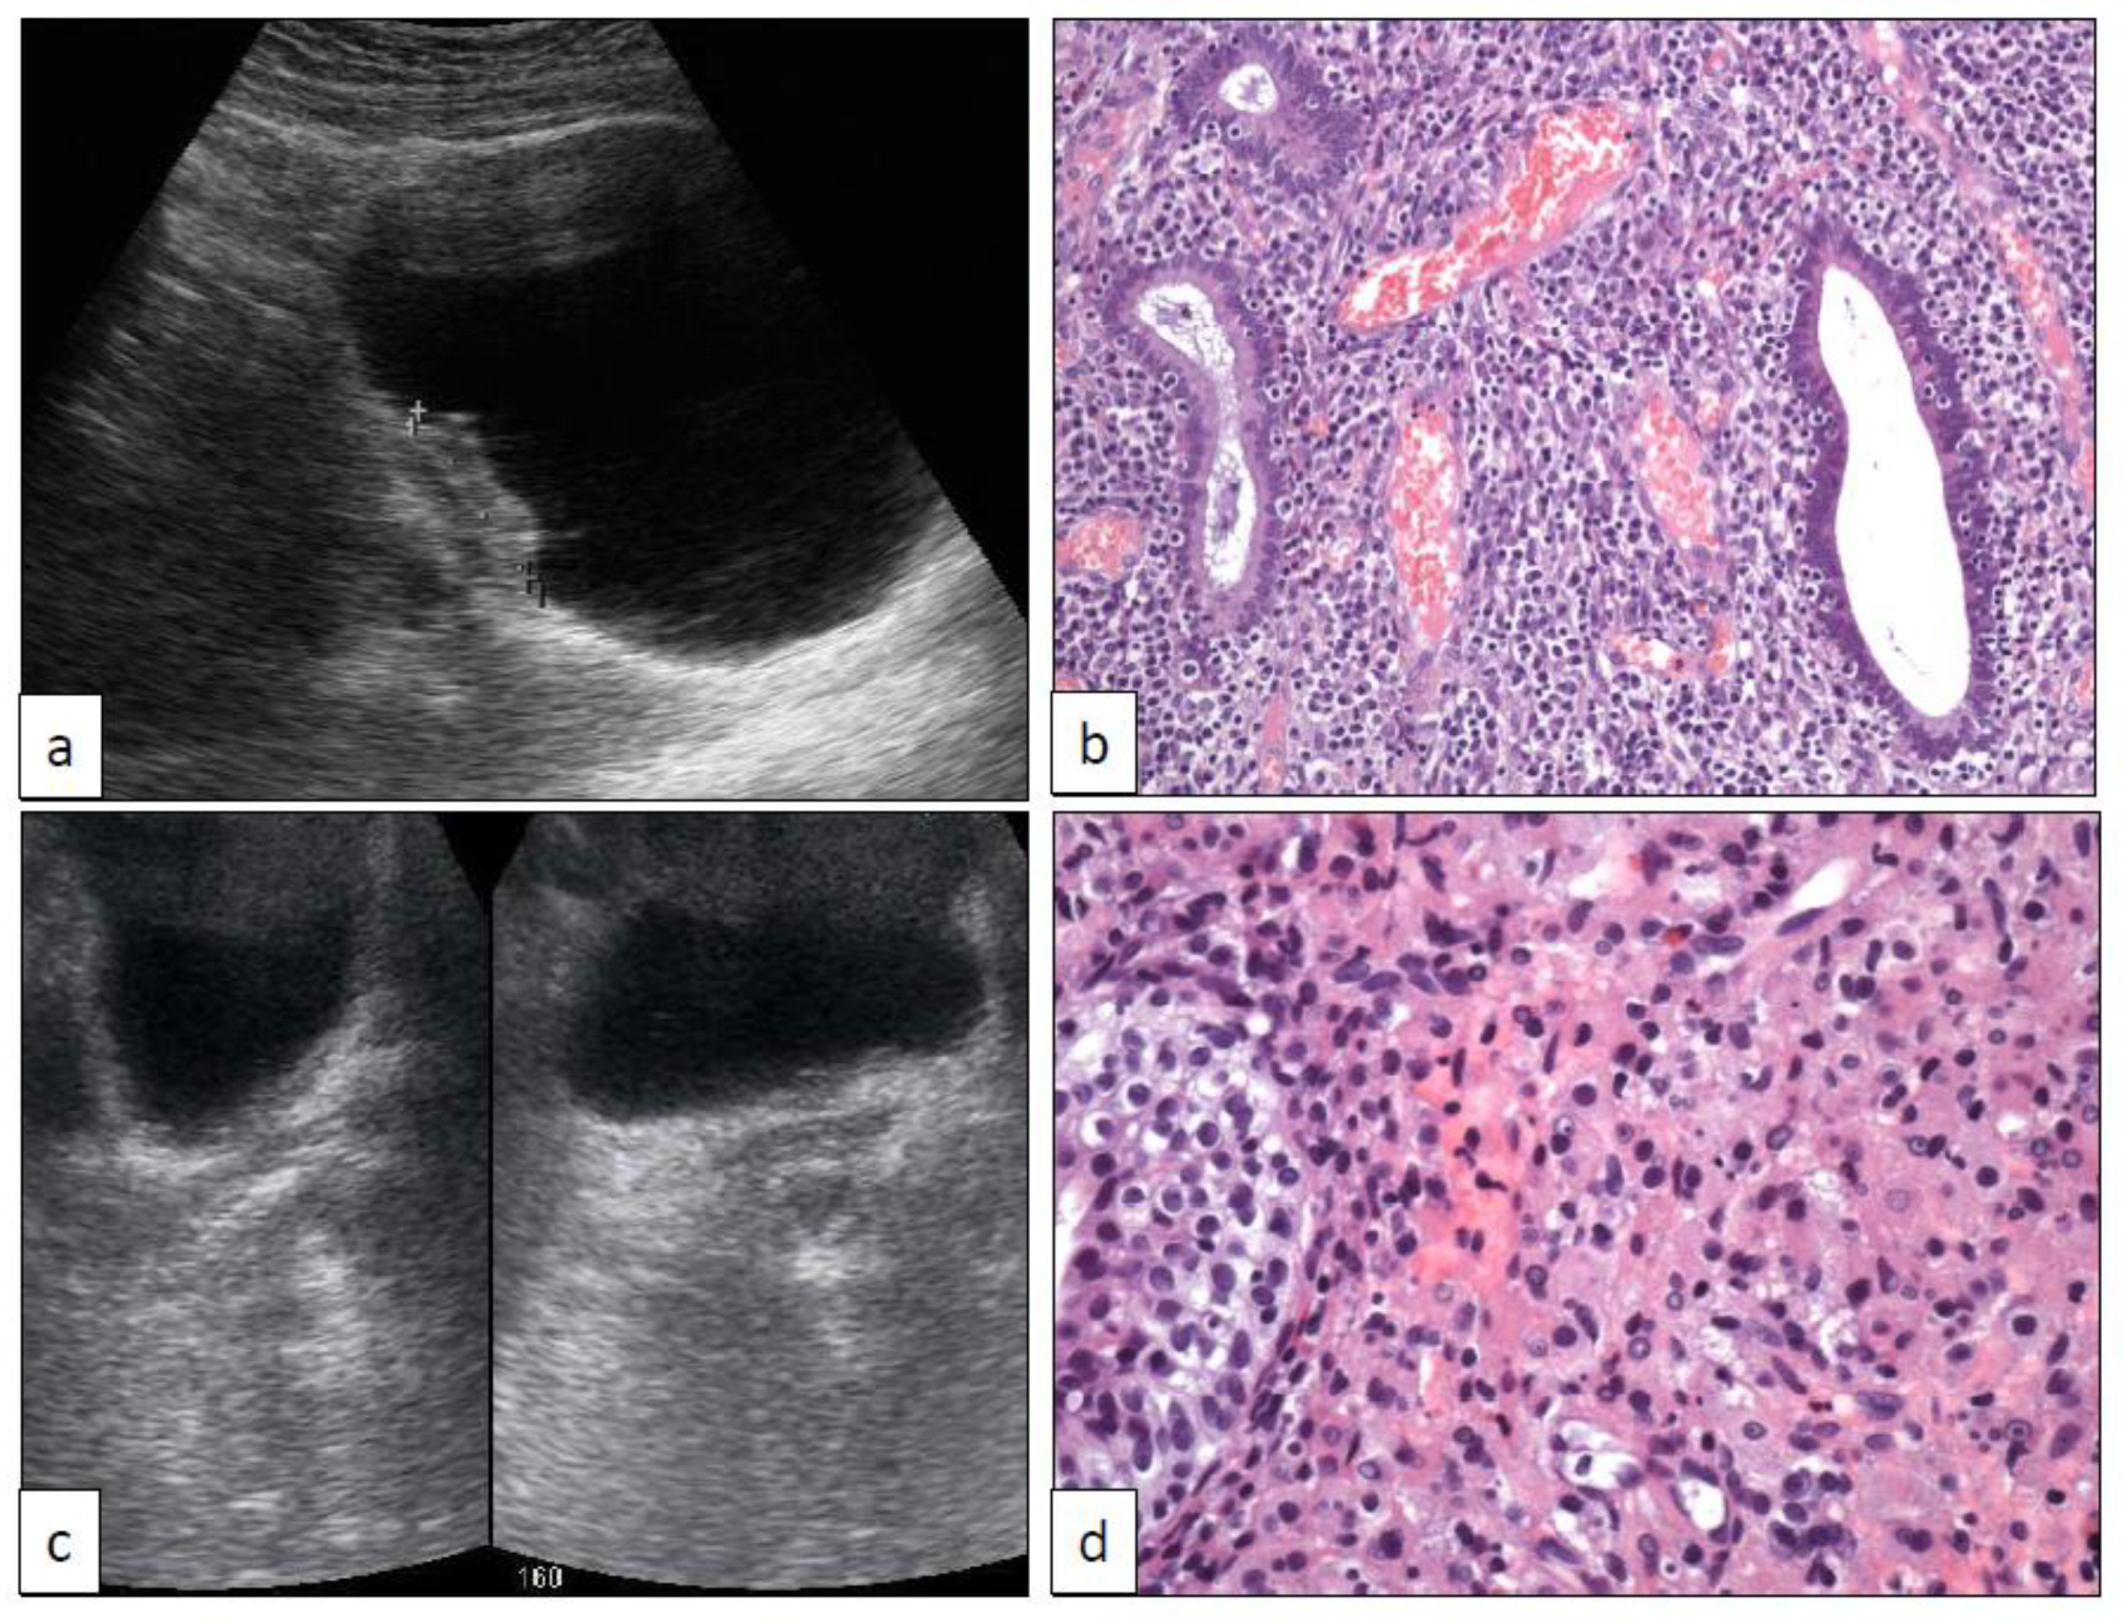

6. Xantho-Granulomatous Inflammation (XI)